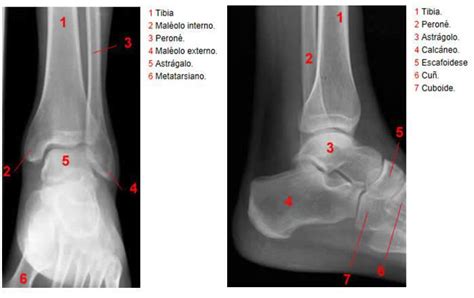

1. Lesiones y Traumatismos

Una lesión en el pie o tobillo es una causa directa de hinchazón en esa área. Por ejemplo, un esguince de tobillo, que ocurre cuando los ligamentos se estiran o desgarran, puede provocar una inflamación significativa. El tratamiento para este tipo de lesiones suele implicar la elevación del miembro afectado, evitar la carga de peso sobre la pierna lesionada, la aplicación de hielo y el uso de vendas de compresión para reducir la hinchazón. Los analgésicos de venta libre pueden aliviar el malestar. Si la hinchazón y el dolor persisten, es necesario un examen médico para descartar daños más graves.